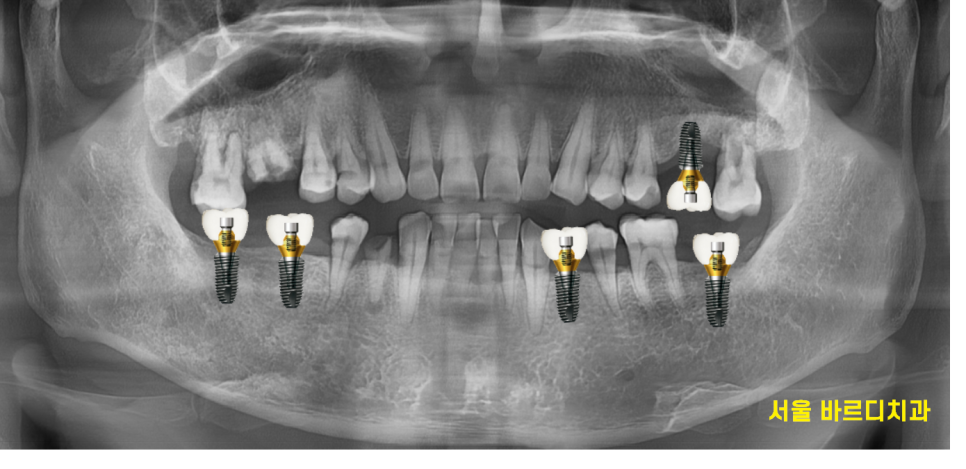

어금니 빠짐 부분을

3차원적으로 분석을 하고

치료 계획을 세워드렸습니다.

23.02.23

망월동 임플란트 수술 직후 사진입니다.

환자분이 한 번에 끝내고 싶다고 하셨는데요.

미리 ct를 통해 분석하고 수술을 해서

당일에 8개 임플란트를 심었지만

1시간 정도 걸렸습니다.